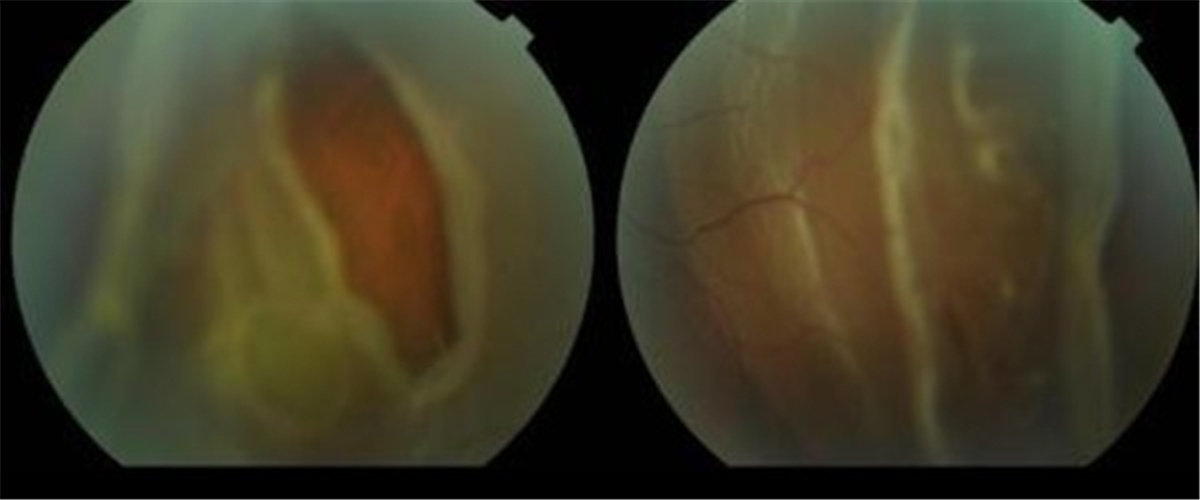

早產兒視網膜脫落

早產兒牽拉性視網膜脫落